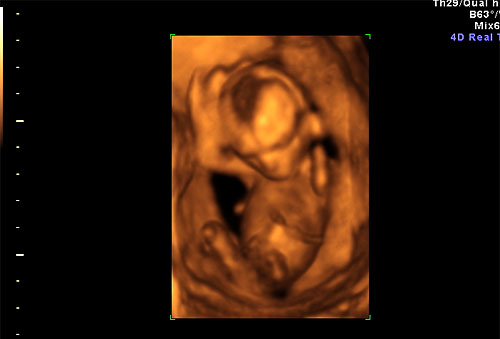

3D ultrasound of 16 week fetus |